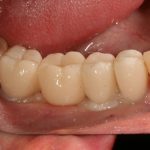

Через неделю я снял швы, а мой коллега Андрей Карнеев (дело было еще в НИЦ) приступил к изготовлению протезов. На это ушло полторы недели:

Ремарка: Во всех случаях "сложной" имплантации первым делом изготавливаются временные коронки на срок до 12 месяцев. Здесь мы провели остеопластику одновременно с имплантацией - и это вполне катит за "сложную" имплантацию и требует изготовления временных коронок на минимальный срок 6 месяцев.

«Ого, какие классные зубы!» — сказала тогда Зинаида, после чего мы попрощались и договорились встретиться через полгода-год для замены временного протеза на постоянный керамический. Зинаида вернулась домой, в дружественную среднеазиатскую страну.

А дальше всё просто. Я попросил своего коллегу Ивана Алгазина заменить износившиеся временные коронки на постоянные керамические — но с учётом современных реалий и требований:

Серия контрольных снимков на этапах:

Вот так закончилась 12-летняя эпопея Зинаиды с восстановлением зубов на нижней челюсти. Через пару дней она уехала на экскурсию в Санкт-Петербург (на всякий случай, мы попросили задержаться в России, вдруг потребуется коррекция), а оттуда — домой, в дружественную страну. Судя по тому, что она нам пишет — у неё всё прекрасно и хорошо. Зинаида обещает не пропускать профилактические осмотры и наблюдаться у стоматолога по месту жительства.